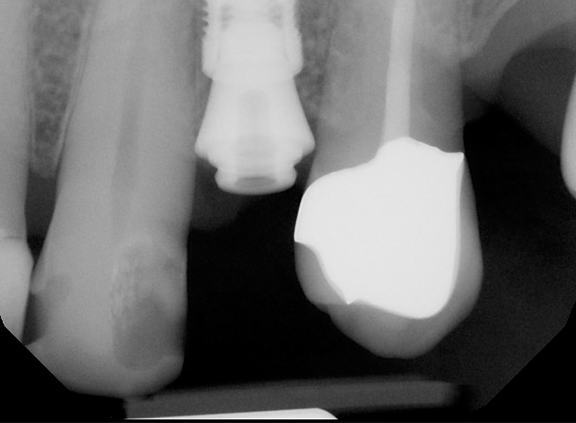

With the final scans complete and the shade for the crown (A4) selected, the patient was ready for the insertion of his new Zirconia implant crown. He consented to proceed, and we carefully tried in the crown, checked and flossed the contacts, and obtained his approval before moving forward with the final placement. The implant crown, a retrievable screw-retained type, was torqued into place with precision, ensuring a secure and stable fit. After confirming the proper seating with a periapical (PA) x-ray, the crown was permanently secured, and the access hole was sealed with resin.